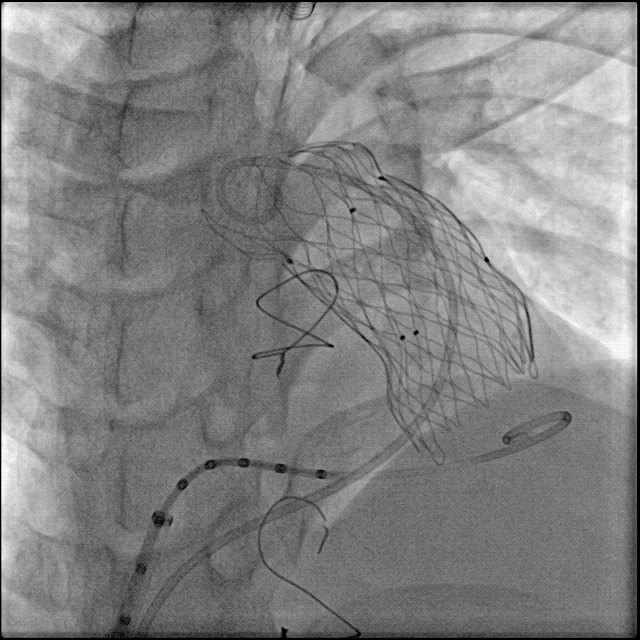

根据术前CT、术中造影及球囊测量结果,选择P34-25型号的VenusP-Valve瓣膜,使用圈套器辅助,沿超硬导丝送输送器至肺动脉分叉处。

缓慢释放瓣膜,造影确认人工瓣膜起始位置准确:

继续释放瓣膜,反复造影确认人工瓣膜位置准确:

人工瓣膜释放完成,缓慢退出输送器:

造影确认无明显瓣周漏: